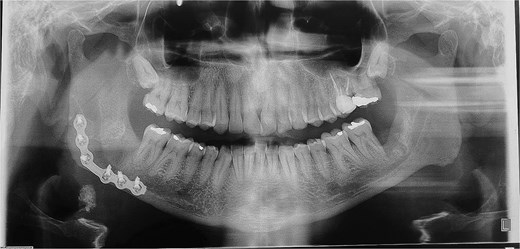

A 49-year-old male patient was referred, after a radiographic finding in a panoramic radiography, for evaluation of the lower right third molar (48) in an ectopic position associated with a radiolucent image, which suggested a cystic lesion (Fig. 1). A cone-beam computed tomography was made. The 3D imaging exams showed the presence of tooth 48 in the mandibular base, in the right angle region, associated with the radiolucent image, lingual fenestration, and intimate relationship between the third molar and the mandibular canal (Fig. 2). Due to the dental position, to have better visualization and less morbidity a submandibular extraoral approach was planned. The tooth removal and cyst curettage were made through the Risdon approach (Fig. 3). A fixation system with reconstruction plate (2.4 mm) was used to prevent a mandibular pathological fracture (Fig. 4). Anatomopathological examination of the cystic capsule was performed with a diagnosis of dentigerous cyst. In the postoperative period, the patient reported alteration in the sensitivity of the inferior alveolar nerve. Postoperative radiographic examinations showed adequate adaptation of the fixation system and complete surgical removal of the tooth and associated lesion. Orthopantomography with 4 months follow-up showed bone repair and adequate adaptation of the fixation system (Fig. 5).

The ectopic third molar usually is asymptomatic and difficult to identify. However, the clinical symptoms include swelling, limited mouth opening, pain, discharging fistula, or temporomandibular joint discomfort [4, 6, 10]. The diagnosis of ectopic third molar is completely formed with radiographic findings such as panoramic radiograph or computerized tomography, that performs 3-dimensional information and precise location of the ectopic tooth and surrounding structures [5, 11]. The panoramic radiography showed the location of the third molar in the present case, but only after the cone-beam tomography examination the treatment plan was defined. The lingual position, the close relationship with the mandibular canal and the caudal position determined the removal through the submandibular approach.